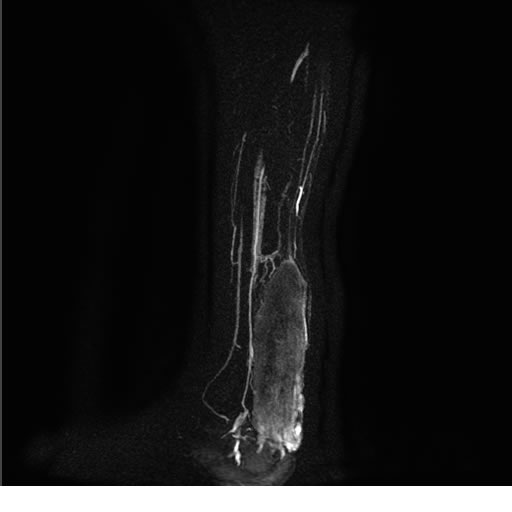

Se realiza estudio de MRI de pierna izquierda, utilizando secuencias Spin Echo y GRE en diferentes planos, se realiza angio MRI en fase arterial y venosa de pierna izquierda

El estudio demuestra masa a nivel de los músculos gemelos, más evidente en secuencia con pulso de saturación de grasa, en el estudio de angio resonancia de pierna la fase arterial no muestra ninguna anormalidad, en la fase venosa se observa acumulo del medio de contraste a este nivel.

Se concluye que se observa una masa de tejido muscular sumamente vascularizada compatible con un hemangioarcoma.